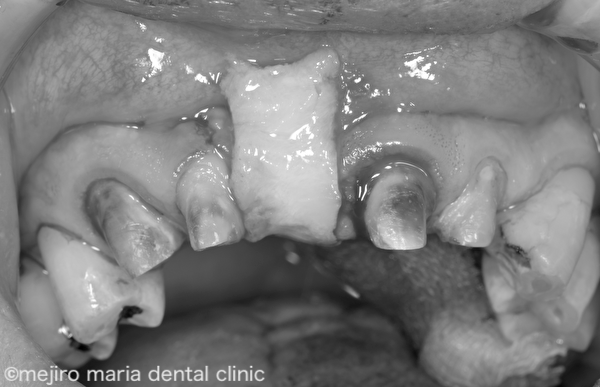

右上3〜左上2までのブリッジが装着されており、欠損部である右上1の歯肉は大きく凹んでしまっています。また、歯肉に対して適合の悪いブリッジが作製されており、歯肉には著明な炎症所見が認められます。この状態では適切に清掃を行い健康な歯肉を維持することはできないでしょう。

上記Before画像を見ると、欠損部である右上1の歯肉が大きく陥凹しているのがわかります。この凹んだ歯肉に合わせてブリッジが作製されていたために機能的、審美的な障害が生じていました。